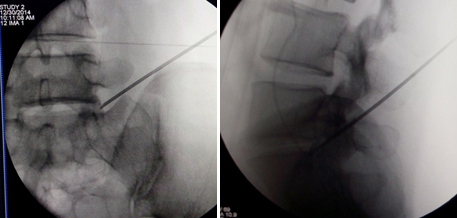

(图)体表定位

(图)穿刺针定位

(图)置入扩张管

(图)术中